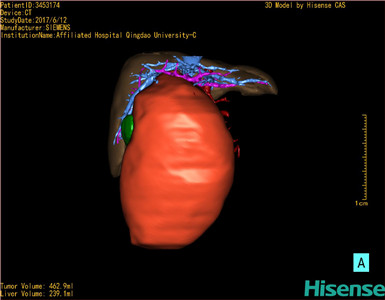

将0.625mm双源薄层CT资料的静脉期和动脉期Dicom格式文件导入海信CAS系统。

通过调节窗宽窗位调整CT序号,对肝实质,胆囊,下腔静脉,肿瘤,肝动脉、门静脉及肝静脉等进行三维重建;系统自动计算肝脏体积。

模拟手术操作,自动计算切除肿瘤体积。肝脏体积为310.9ml,肿瘤体积为437.7ml,肿瘤体积是肝体积的1.4倍,通过比对9-12月正常肝脏体积为321.13±118.91ml,通过术前模拟手术,精准判断切除后剩余肝脏体积能耐受,避免肝衰竭发生。

术前三维重建:

重建图片